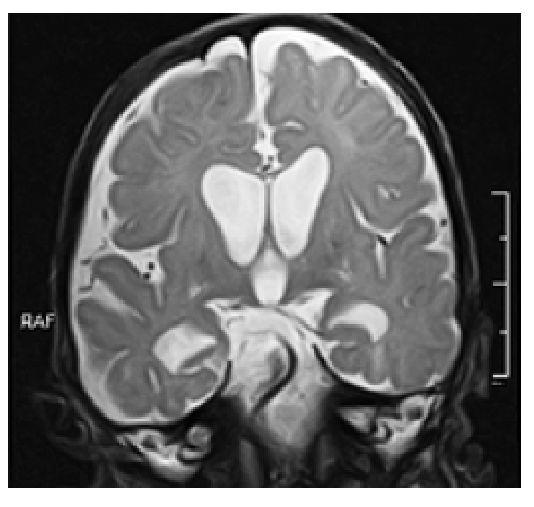

3. Коронарная проекция - по слуховым нервам (рис. 3).

Рис. 3. Пример позиционирования срезов по слуховым нервам аксиальной плоскости для получения изображения в коронарной проекции при проведении магнитно-резонансной томографии головного мозга на примере Т2 ВИ пациенту восьми месяцев жизни